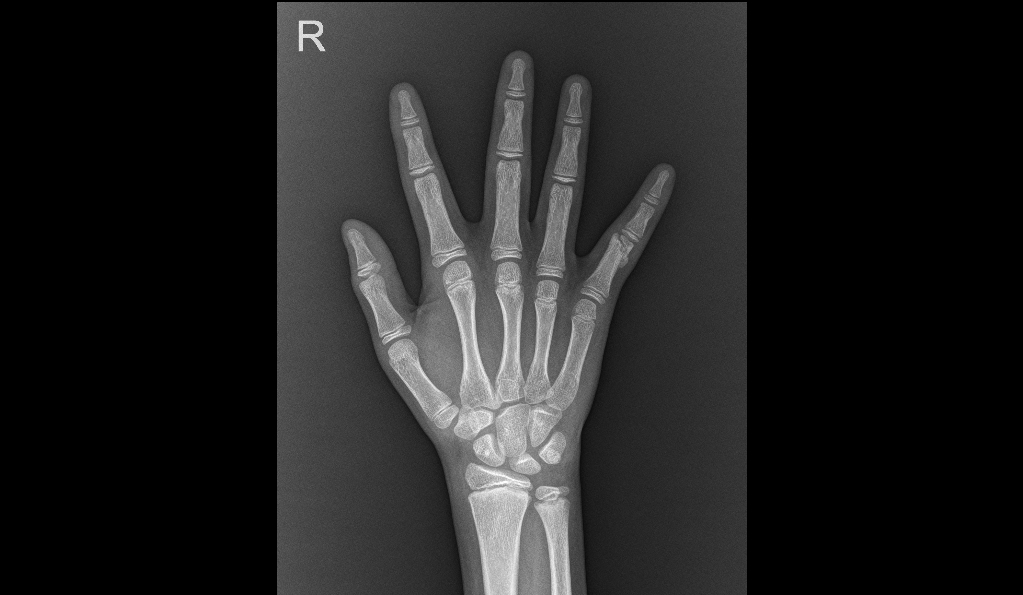

手部指骨骨折在手部损伤中也特别常见,手指指骨骨折损伤手部骨骼,会严重影响手的功能。在排球、篮球类体育运动中或伸手去取某件物品时,手指有时候会戳伤,大部分戳伤只是软组织挫伤,无须手术和固定即可康复。但是当出现以下症状时需要警惕并尽早就诊: